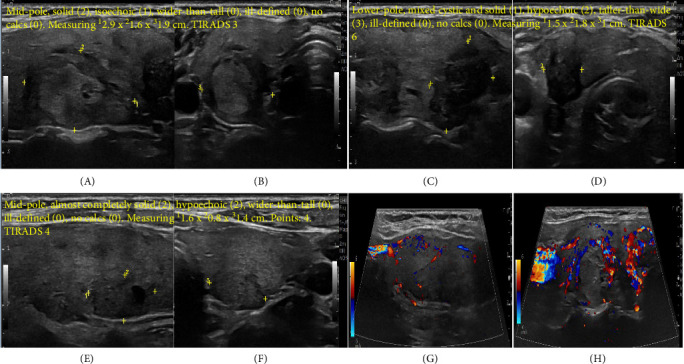

Marine-Lenhart syndrome (MLS) is a rare condition characterized by the coexistence of hyperfunctioning thyroid nodules and Graves' disease (GD). The prevalence of thyroid nodules and thyroid cancer is higher in patients with GD. We report a case of 42-year-old female who presented with thyroid storm and found to have underlying GD. An initial thyroid ultrasound (US) revealed two nodules classified as TIRADS 3, whereas a repeat US after achieving euthyroidism, showed changes in the size and consistency of these nodules and identified a new nodule with classification of TIRADS 6 nodule. A 24-h radioactive iodine thyroid uptake scan demonstrated a diffuse increase uptake (75.1%) with one hyperfunctioning and two warm nodules, including the newly identified TIRADS 6 nodule. Fine-needle aspiration (FNA) biopsy confirmed papillary thyroid cancer (Bethesda VI) in a right (R) warm nodule (the TIRADS 6 nodule), while the other two nodules were benign (Bethesda II). The patient underwent a R hemithyroidectomy that was complicated by recurrent laryngeal nerve (RLN) injury. Pathology examination revealed unifocal papillary thyroid microcarcinoma with positive anterior surgical margin. The patient was furtherly treated with radioactive iodine therapy thyroid nodules with GD should be managed cautiously. Emerging evidence challenges the previous notion that hyperthyroidism provides protection against thyroid cancer. The association between GD and thyroid malignancy remains an area of ongoing investigation, with variable management strategies and prognostic implications reported in the literature.